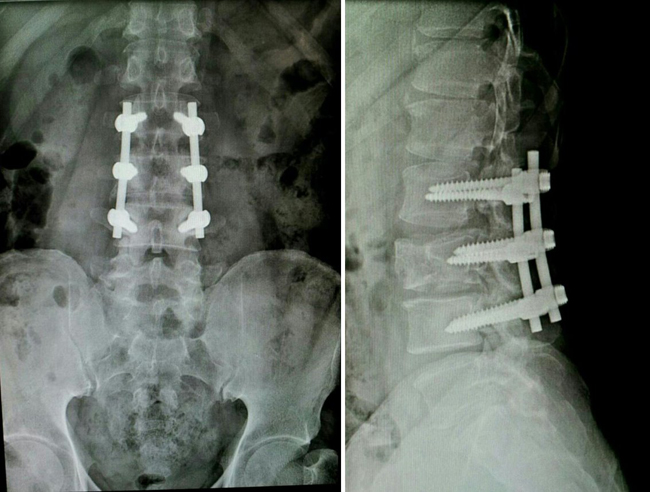

정오영 도생의 허리. 2011년 8월13일 전봇대 감전으로 추락사고를 당해 허리 아랫부분을 크게 다쳤다. 사고 3일만에 수술하여 이런 모습이 되었다. 사진은 치료 과정에서 2014년 정형외과 전문병원인 수병원(서울 소재)에서 촬영한 허리 아래부분 X레이. 수술 후에도 계속 치료를 했으나 고통은 여러 해 계속됐다. “허리에 늘상 얼음기둥을 꽂아 넣은 듯 시리고 아픕니다. 그 고통을 겪어보지 못한 사람은 상상도 할 수 없을 것입니다.” 이런 극심한 통증이 태을주 도공수행으로 거짓말처럼 사라졌다.